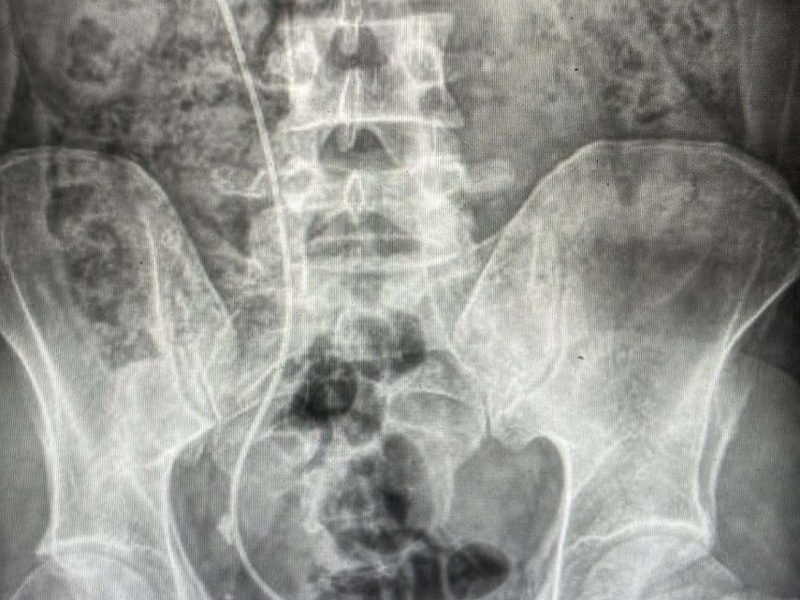

Litiasis urinaria. Estudio metabólico en pacientes afectados. Congreso Nacional de Urología LXXXVIII Reunión Nacional de los Grupos de Litiasis, Endourología,…